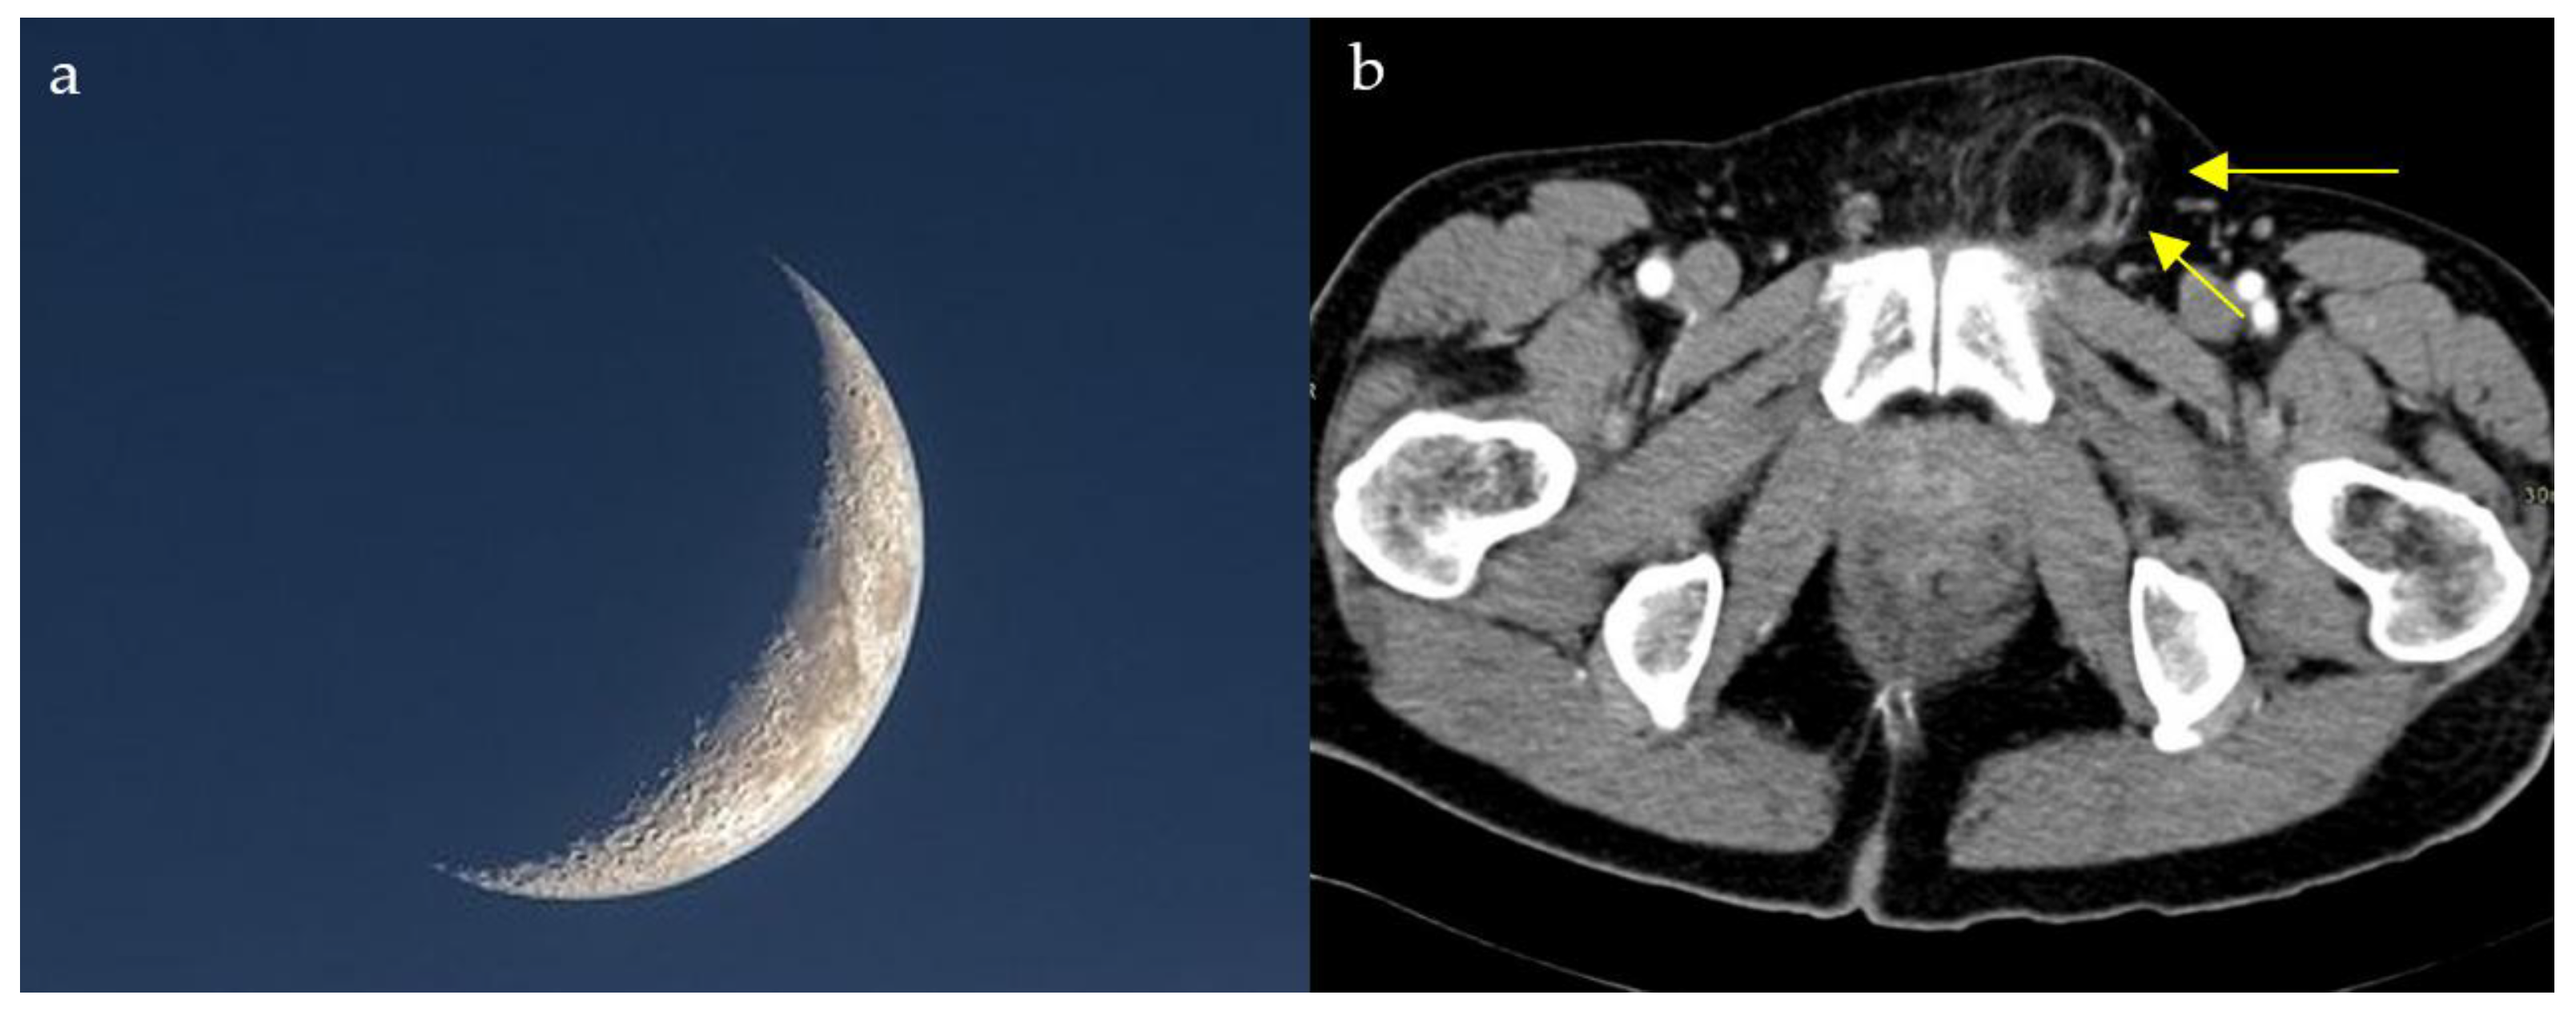

2.13. Lateral Crescent Sign

Distinguishing direct and indirect inguinal hernias on CT scan can be challenging due to the intricate anatomy at the level of the inguinal area. The lateral crescent sign is seen in the setting of direct hernias and is, therefore, helpful for making this distinction. Direct inguinal hernias project through the Hesselbach triangle, an area bordered by the lateral edge of the rectus muscle medially, the inguinal ligament inferiorly, and the inferior epigastric vessels laterally. The compression of the inguinal canal content as well as fat gives the appearance of a characteristic flattened crescent shaped structure resembling a crescent moon (Figure 13a,b) [63]. In a small comparative CT series, the lateral crescent sign identified direct inguinal hernias, with a sensitivity of 69% and a specificity of 80%, supporting its utility while underscoring the need for validation in larger cohorts [64]. Patients with groin swelling, pain, or symptoms of bowel obstruction may show a lateral crescent of compressed tissue adjacent to a direct inguinal hernia on CT. This finding distinguishes direct from indirect hernias, guiding appropriate surgical repair.

Figure 13.

Compression and lateral displacement of the inguinal canal contents by the hernia to form a semicircle of tissue seen lateral to the hernia on axial CT images of the pelvis (yellow arrows) (b), resembling a crescent moon (a).